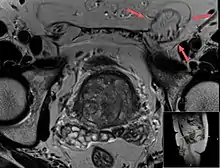

T2 weighted MRI of the same case (done for another purpose), also demonstrating fat content.

An indirect inguinal hernia results from the failure of embryonic closure of the deep inguinal ring. In the male it can occur after the testicle has passed through the deep inguinal ring. It is the most common cause of groin hernia. A double indirect inguinal hernia has two sacs.

When assessed by ultrasound or cross sectional imaging with CT or MRI, the major differential in diagnosing indirect inguinal hernias is differentiation from spermatic cord lipomas, as both can contain only fat and extend along the inguinal canal into the scrotum.[22]

On axial CT, lipomas originate inferior or lateral to the cord, and are located inside the cremaster muscle, while inguinal hernias lie anteromedial to the cord and are not intramuscular. Large lipomas may appear nearly indistinguishable as the fat engulfs anatomic boundaries, but they do not change position with coughing or straining.[22]